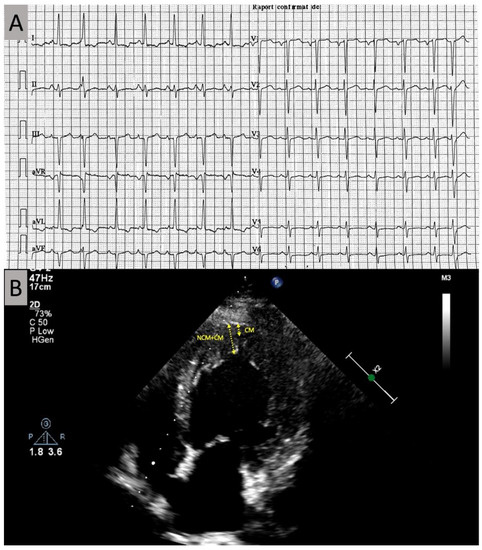

2. Case Presentation

2.1. Investigations